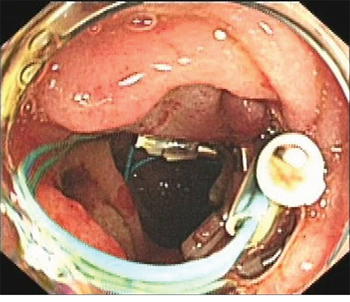

An Olympus double-lumen endoscope (Olympus, Center Valley, PA, USA) was used to attempt repair; however, the diameter of the injury was too long. A titanium clip was used to attempt closure of the perforation, but this technique failed. Therefore, an endoscopic purse-string suture was employed. First, the double-lumen endoscope was used to observe the location, size, and appearance of the injury. Then, the following steps were taken: (1) a nylon ring and a titanium clip were inserted along the double channels of the endoscope; (2) after adjusting the angle and location of the nylon ring and titanium clip, the first titanium clip was used to hold the distal end of the nylon ring vertically, firmly approximating the normal mucosa at the distal edge of the defect, and fixing it by deploying the clip (Figure 3); (3) several titanium clips were placed along the nylon string, around the perforation; (4) the last clip was inserted to hold the proximal end of the nylon ring, approximating and fixing it to the normal mucosa at the proximal edge of the defect; and (5) the nylon ring was retracted to draw the distal and proximal edges of the mucosa of the wound together. Endoscopy demonstrated that the perforation had been successfully closed (Figure 4). Postoperatively, a jejunal feeding tube and gastrointestinal decompression tube were placed; she was maintained on bowel rest and placed on antibiotics. Two days later, her abdominal pain was relieved, her abdominal tenderness was significantly reduced, and no rebound tenderness was demonstrated on examination. Subcutaneous emphysema was absorbed after 5 days. Enteral nutrition was initiated 5 days postoperatively. As there was no free intraperitoneal air on plain radiographs 10 days postoperatively, the gastrointestinal decompression tube was removed. After 3 weeks, the jejunal feeding tube was removed and the patient was discharged. At her 2-month follow-up visit, she had no complaints or symptoms.

Figure 4: Complete closure of the perforation.